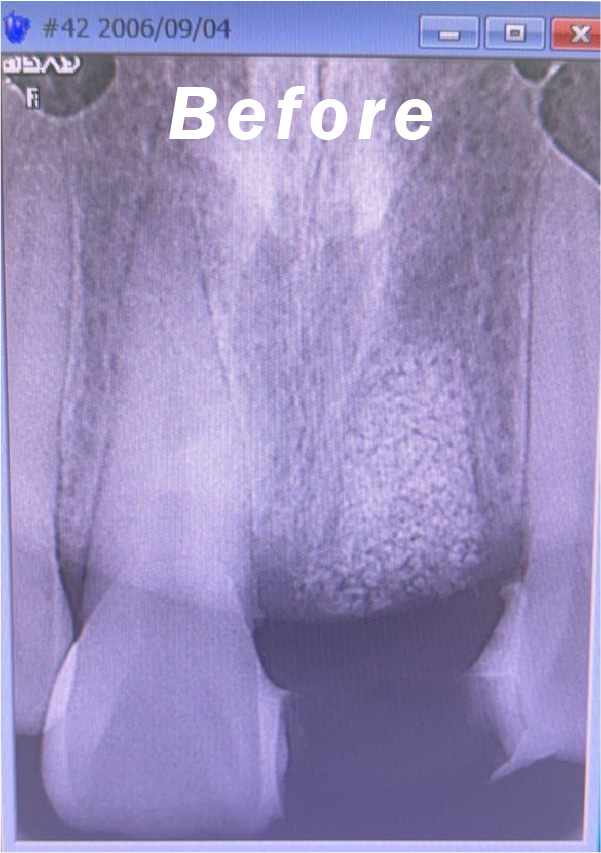

症例のbefore画像

治療内容 インプラント

治療期間 3ヵ月

性別/年代 男性/40代

治療費 350,000円(税別)

治療のデメリット 保険が効かないため自費診療になり、外科手術が必要。又、治療期間が下顎で3ヶ月上顎で4〜5ヶ月の治療期間を要します。

インプラント術前、術後のレントゲンと口腔内写真です。術後18年の症例です。状態は良好です。